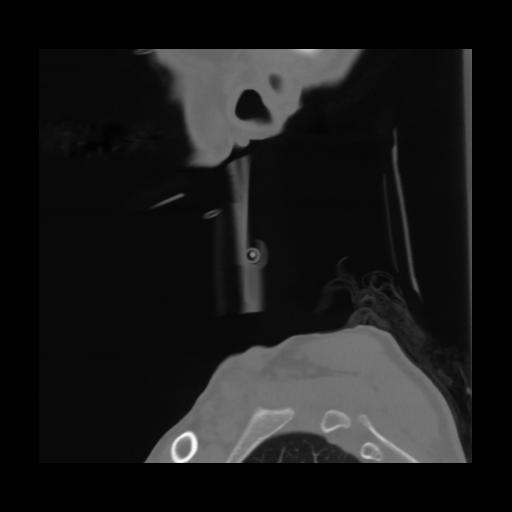

14 P.BLANDAS,,Sagittal,2.000,P.BLANDAS,Sagittal,